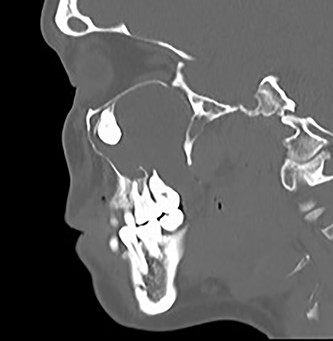

A 29-year-old female patient was referred from the Maxillofacial surgeons to ENT outpatients, for assessment of a loose upper right molar and right-sided retro-orbital pain, ongoing for 4 months. She had no past medical or surgical history and was a lifelong non-smoker with no significant family history. Imaging with a orthopantomogram (Fig. 1) depicted an ectopic tooth in the right maxillary sinus. CT imaging further characterized a thin-walled cystic mass in the right maxillary sinus (Figs 2 and 3), and opacification of the maxillary and ethmoidal air cells is also visualized alongside the afore mentioned ectopic tooth.

Sagittal CT image of the right ectopic tooth at the antrum of the right maxillary sinus.